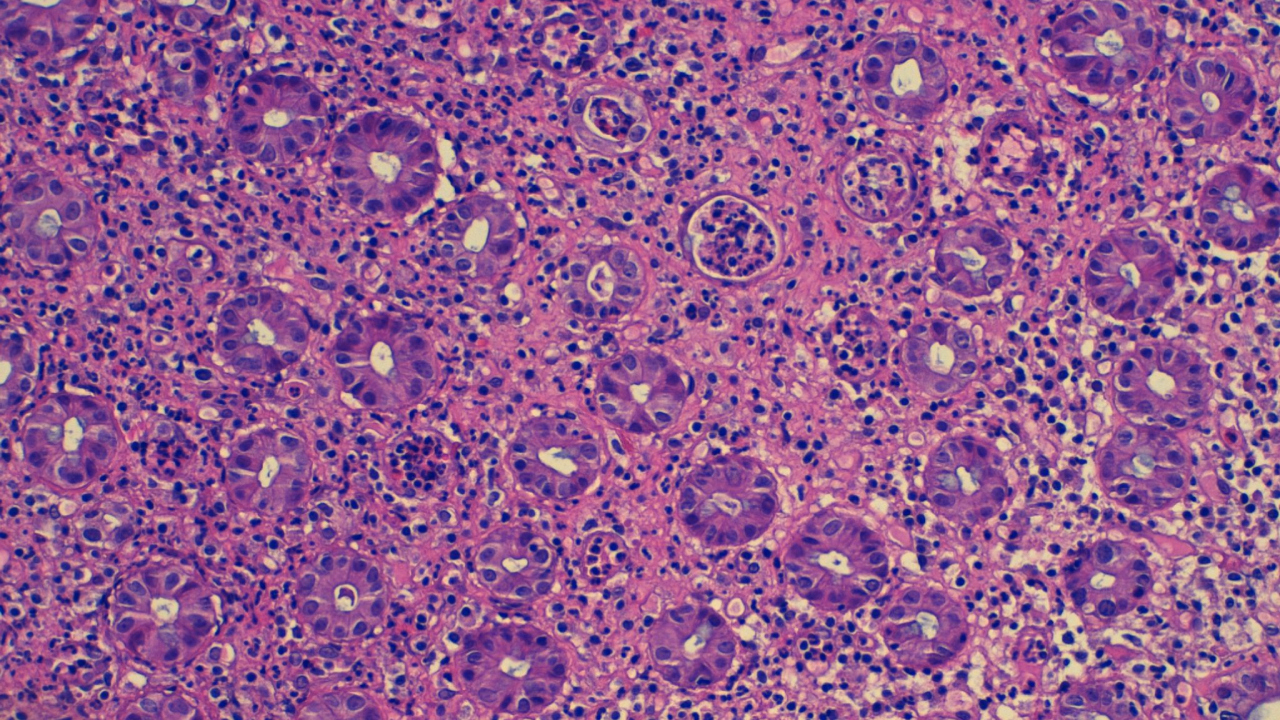

Antiguamente, el patólogo era una persona de laboratorio dedicada al microscópico, que con la ayuda del microtomo, la parafina y los cortes obtenidos y teñidos con diferentes coloraciones, hacia un diagnóstico.Inicialmente solo utilizando la tinción de hematoxilina eosina, que aun hoy en día sigue siendo el goldstandard, y posteriormente, ayudándose de las tinciones de inmunohistoquímica, así como de la homogenización y rapidez de todo el procesamiento de las muestras para mejorar la precisión y rapidez diagnóstica.